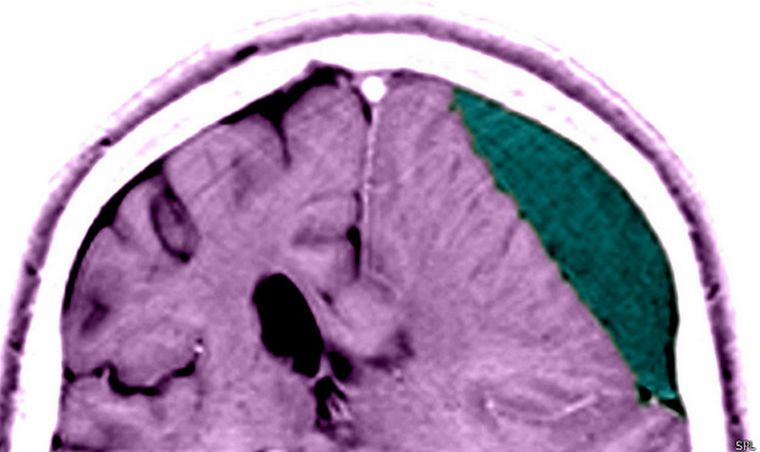

Las personas que más educación académica han recibido parecen tener más probabilidades de recuperarse de un traumatismo craneoencefálico moderado o severo, lo cual sugiere que lo que se conoce como "reserva cognitiva" del cerebro puede tener un papel importante en el proceso de recuperación del paciente.

Tras revisar el estado de salud de los pacientes un año después de sufrir dicho traumatismo craneoencefálico, los investigadores han constatado que aquellos pacientes que poseían los conocimientos equivalentes a por lo menos una carrera universitaria tuvieron siete veces más probabilidades de recuperarse del traumatismo craneoencefálico y dejar atrás las discapacidades que éste les provocó, en comparación con quienes no terminaron la escuela secundaria.

Los resultados, aunque representan una novedad médica en el campo del traumatismo craneoencefálico, reproducen la misma tendencia ya observada en investigaciones previas sobre la enfermedad de Alzheimer, en la cual el nivel de educación académica del paciente (que se toma como referencia del nivel de conocimientos acumulados y del grado de robustez de la "musculatura" cerebral y por ende de la magnitud de la reserva cognitiva) está relacionado con la velocidad a la que progresa la enfermedad. A mayor nivel de educación académica, más despacio avanza la dolencia.